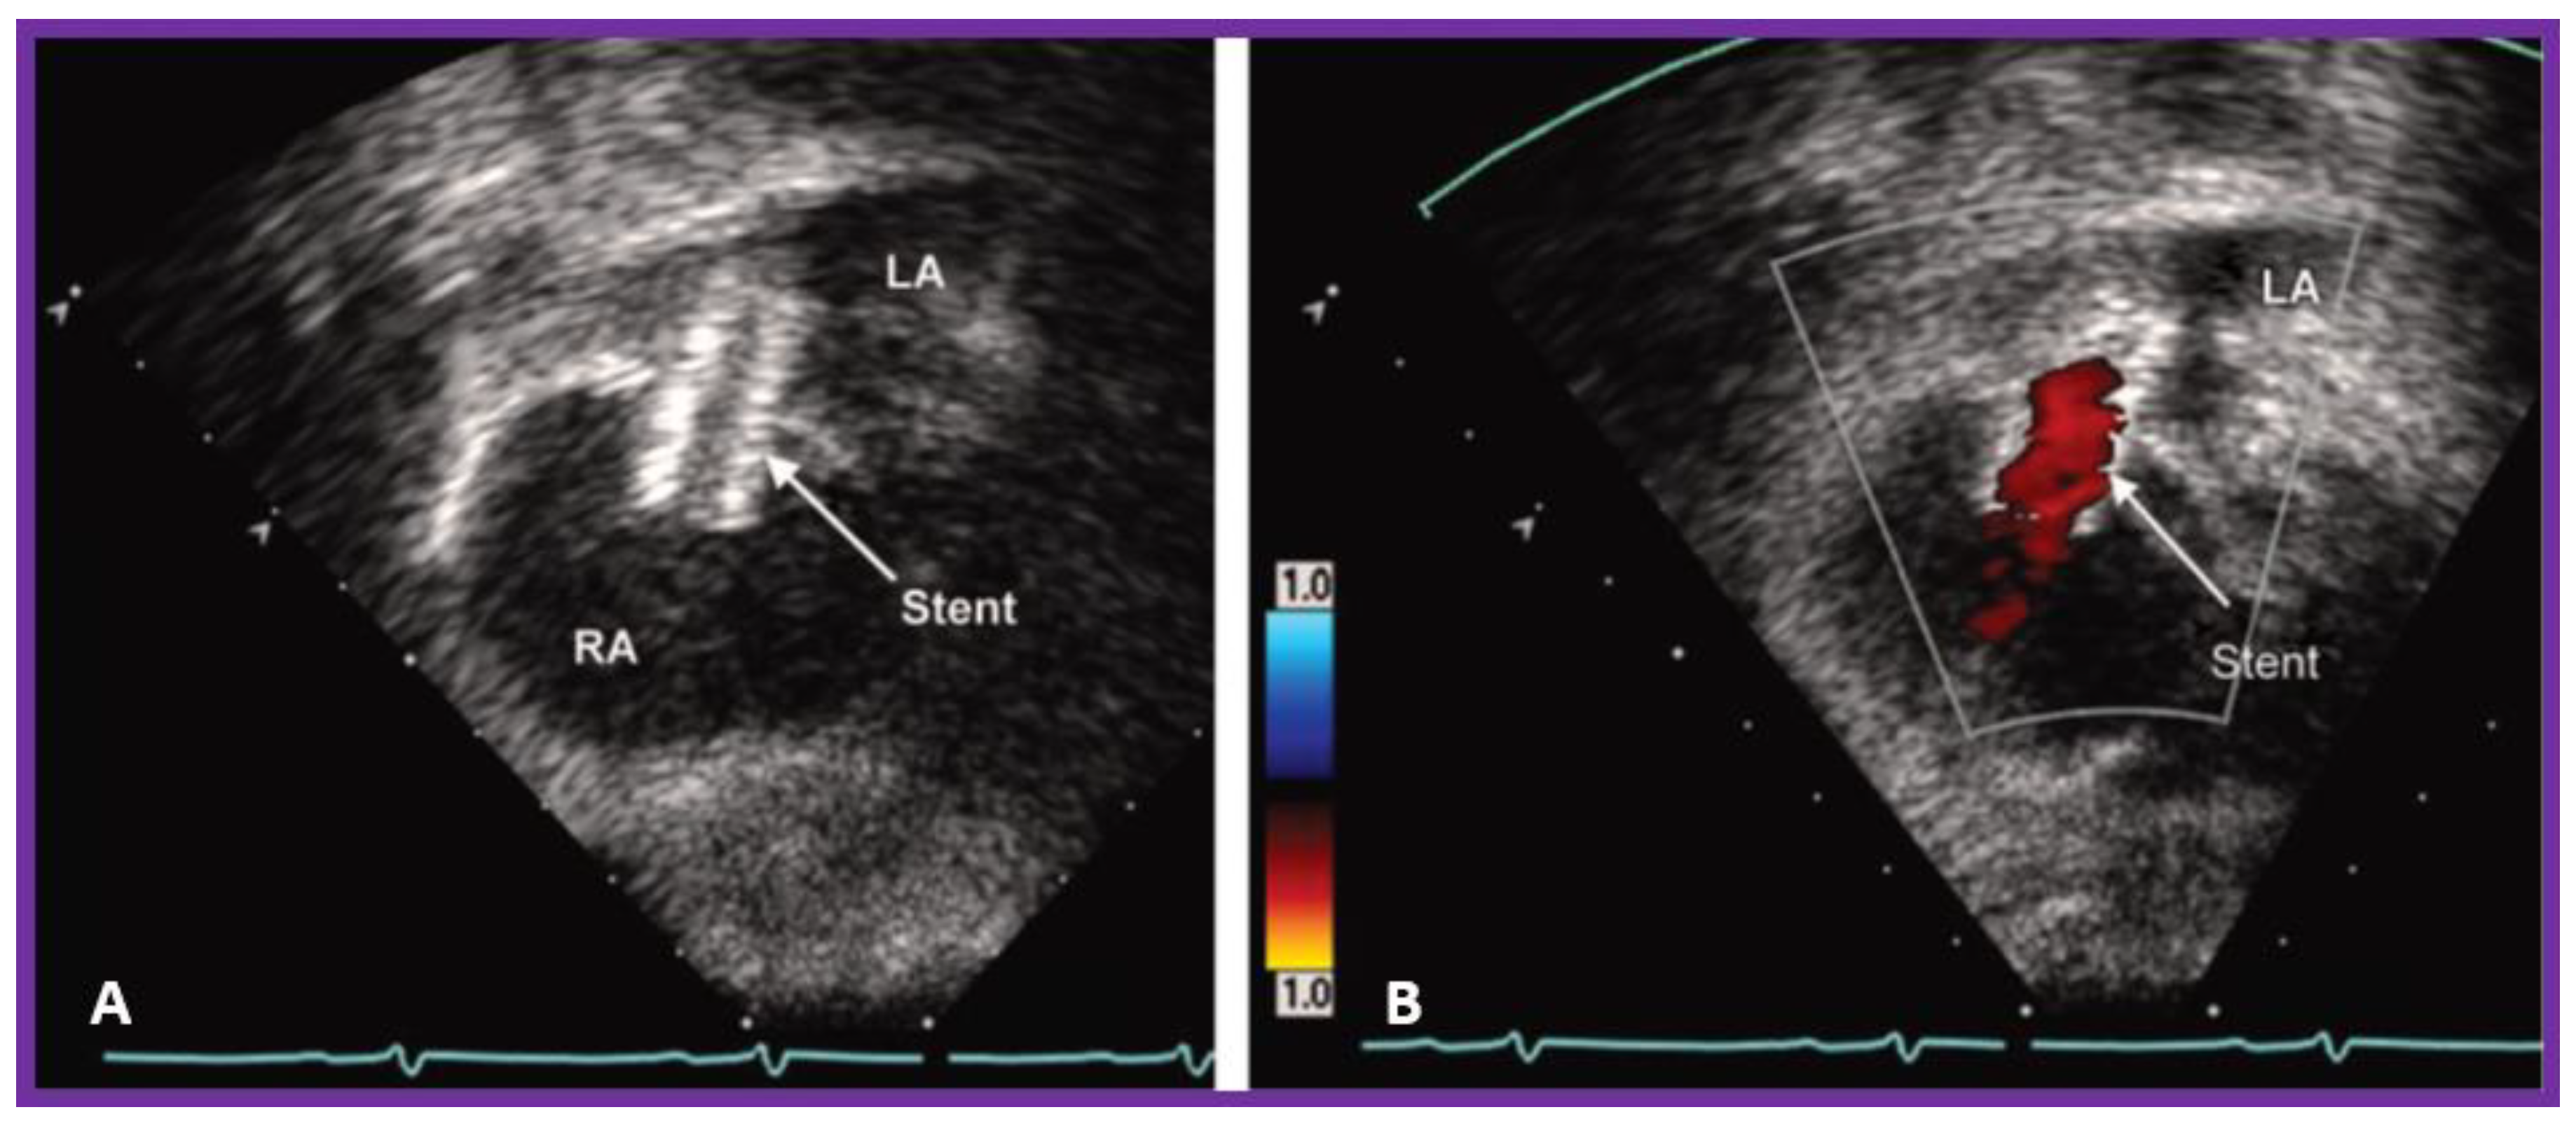

10.1.1. Inter-Atrial Obstruction